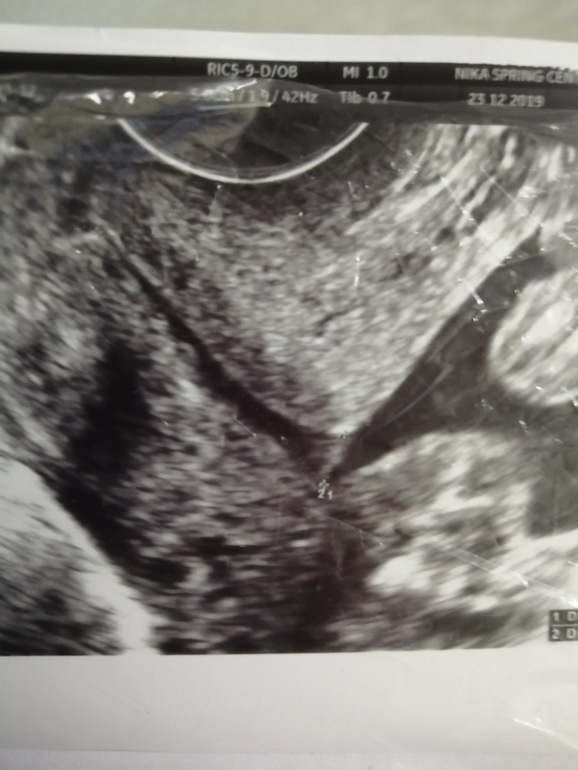

В 15 недель ШМ была 41,5 и был расширен цервикальный канал 1,6 на всем протяжении. Зевы закрыты.

Сегодня ровно 19 недель, ШМ 28 внутренний зев открыт 4,6 мм Цервикальный все так же расширен.